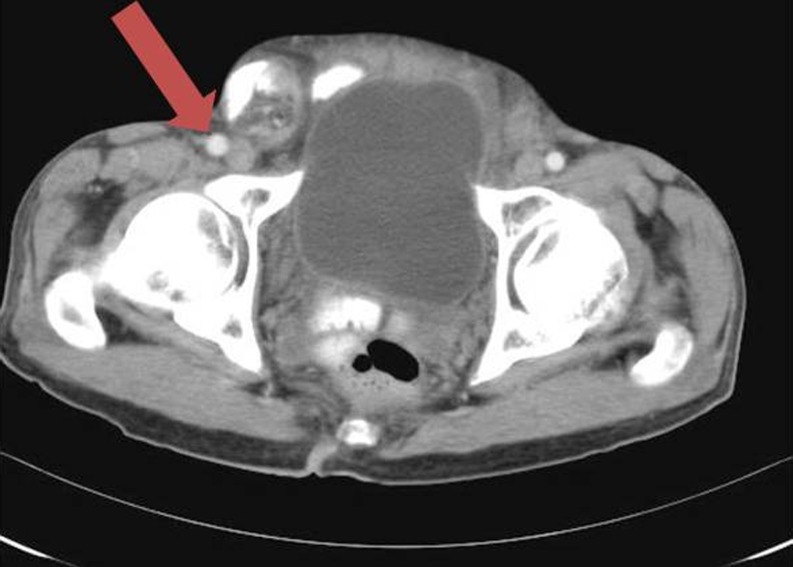

Spigelian Hernia

Spigelian hernia is a rare acquired interparietal hernia, accounting for less than 2% of all anterior abdominal wall hernias [17–19]. They are usually seen in women above the age of 50 years and who are often overweight. It is due to defect of the aponeurosis between the transverses abdominis and the rectus muscle (Fig. 6).

Fig. 6.

Spigelian hernia. CT scan shows herniation of opacified bowel loops (arrow) and mesenteric fat through a defect of aponeurosis between right rectus abdominus and aponeurosis of right transverse abdominus. Lateral margin of hernial sac is the intact external oblique muscle and fascia

They are seen external to the rectus muscle and inferior to the external oblique muscle in the area between the umbilical scar and the anterosuperior iliac spine along the semilunar line. Computed tomography confirms the diagnosis when the external oblique aponeurosis is defective and the subcutaneous hernial sac may be confused with a lipoma of the abdominal wall [11, 19].